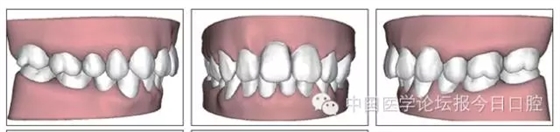

本病例為慢性牙周炎致前牙漂移、深覆(牙合)患者。本病例采用無托槽隱形矯治技術進行治療。無托槽隱形矯治器具有可摘戴、便于口腔衛(wèi)生維護和牙周治療的優(yōu)點,更適合于伴有牙周炎的錯(牙合)畸形患者的治療。 患者男,48歲,前牙有縫、前突求診。 患者面部對稱,側(cè)面觀上頜前突,下頜后縮。 口內(nèi)情況:恒牙列,24、34、44缺失,磨牙Ⅲ類關系,上牙列散隙,上前牙扇形漂移。前牙深覆(牙合)、深覆蓋??谇恍l(wèi)生較差,11與12間牙齦乳頭紅腫,多個牙探診有牙周袋形成,11松動Ⅰ度,余切牙松動(-),患者面像及口內(nèi)像如圖1、2所示。 圖1 治療前面像 圖2 治療前口內(nèi)像 全口曲面體層片(圖3)顯示,患者全牙列牙槽骨吸收;根尖片(圖4)示11近中牙槽骨角形吸收已達根尖1/3,21牙槽骨嵴頂吸收至根1/2,23牙槽骨近中骨板角形吸收至根1/2。磨牙區(qū)骨嵴頂吸收3mm。治療前頭顱側(cè)位片見圖3,治療前ODS模型見圖5。 圖4 治療前根尖片 圖5 治療前ODS模型 牙型:安氏Ⅲ類。骨型:Ⅱ類。面型:上頜前突,下頜后縮。 問題列表為:①上牙列間隙;②上切牙病理性牙移位;③前牙深覆(牙合)、深覆蓋;④24、34、44缺失;⑤慢性牙周炎。 矯治目標包括:①排齊牙列,關閉牙列間隙;②改善前牙深覆(牙合)、深覆蓋;③改善牙周狀況。 矯治設計有:①牙周基礎治療與維護。②壓低、內(nèi)收上切牙,關閉上牙列間隙。③壓低下切牙,伸長下后牙,整平Spee曲線,改善前牙覆(牙合)、覆蓋。 患者進行全口齦上潔治、齦下刮治,口腔衛(wèi)生宣教,并按牙周醫(yī)師的要求,每2~3個月行牙周檢查與治療。 牙周基礎治療結(jié)束3個月,開始隱形矯治。于14、25、35、36、45、46上粘接附件(圖6),于16、26(牙合)面粘接(牙合)墊。 圖6 ODS設計附件粘接圖示 矯治過程中注意(牙合)墊是否脫落或磨損,及時修補。 注意上前牙內(nèi)收時有無咬合干擾,及時調(diào)(牙合)。下頜前磨牙伸長到位后,磨除16、26(牙合)墊。 下頜佩戴第24步矯治器時,分別在36、37、46、47的頰、舌側(cè)粘接舌扣,矯治器上預留伸長空間,用3/16英寸、3.5盎司皮圈牽引,輔助伸長下磨牙(圖7)。 患者共戴用矯治器上頜32步,下頜26步。 矯治后,牙列間隙關閉,面型及覆(牙合)覆蓋改善。11根尖片(圖8)顯示,治療后較治療前,牙周支持組織增加,牙槽骨角形吸收區(qū)水平向縮小0.3mm,垂直向縮小0.6mm。11松動Ⅰ度,余切牙無松動。 圖8 治療后根尖片 圖9 治療后口內(nèi)像 圖10 治療后X線檢查 圖11 治療后ODS模型 正畸-牙周聯(lián)合治療對于牙周組織的影響 多學科綜合治療牙周炎患者不再是正畸治療的禁忌證。良好的牙周治療為正畸治療中的牙齒移動打下堅實基礎,而正畸治療排齊牙齒、去除(牙合)干擾,有利于牙周健康。 牙周炎患者的正畸治療必須在牙周炎癥得到控制后才能進行,否則,菌斑會隨著牙齒的移動,特別是壓低而使牙周炎癥加重。牙周炎的正確診斷、牙周炎癥控制、正畸治療中和治療后的認真維護是治療成功的關鍵。根據(jù)臨床需要,一般每2~4周做一次潔治,每3個月進行牙周評估,同時患者必須進行非常良好的日??谇恍l(wèi)生維護。 固定矯治器使得牙周檢查、潔治和日??谇恍l(wèi)生維護變得困難,隱形矯治器可自行摘戴,便于患者日常維護和牙周治療,節(jié)約時間,提高菌斑控制效果。 有臨床研究表明,對于存在(牙合)創(chuàng)傷,伴有角形吸收的患牙,經(jīng)過牙周翻瓣手術控制住牙周炎癥后,使用正畸輕力壓低患牙,可以改善牙槽骨吸收的程度,并獲得一定程度的牙周新附著。本病例切牙壓低后,原來的牙槽骨吸收有改善。 病理性牙移位 病理性牙移位(PTM)在重度牙周炎患者中的發(fā)生率為30%~50%,且常見于上前牙區(qū)。其主要由于牙周支持組織喪失尤其是骨組織的丟失,咬合因素(如后牙缺失、前牙深覆牙合、牙合創(chuàng)傷等),頰舌唇肌力量不平衡及牙周和根尖周組織炎癥所致,是牙周炎患者要求正畸治療的主要原因之一。 PTM須通過正畸、牙周聯(lián)合,有時須配合修復才能達到理想的治療效果。正畸治療通常是壓低牙齒,臨床研究表明,牙周手術配合正畸壓低可以產(chǎn)生新附著,有利于PTM牙周組織的恢復。 本病例右上中切牙牙槽骨角形吸收,在盡量保證治療前后根尖片投照角度一致的情況下,以鄰牙作為校準,在根尖片上對治療前后的骨量進行評價,治療后牙槽骨角形吸收區(qū)水平向縮小0.3 mm,垂直向縮小0.6mm。盡管根尖片并不能說明骨量改變,但從影像學上能看到骨吸收區(qū)域有所減小。 無托槽隱形矯治器矯治牙周病的優(yōu)勢 無托槽隱形矯治器具有可摘戴、便于口腔衛(wèi)生維護和牙周治療的優(yōu)點,更適合于伴有牙周炎的錯(牙合)患者的治療;同時,無托槽隱形矯治器佩戴后具有牙弓夾板和(牙合)板的作用,可有效減少側(cè)向力,有利于牙周的恢復和減輕牙齒松動;由于無托槽隱形矯治器的設計是在三維數(shù)字模型上進行的,每個矯治器移動牙齒的數(shù)量和每個牙齒的移動距離可以得到量化控制,因而可以根據(jù)患者牙槽骨水平和對矯治力的耐受情況個性化設計矯治力,并且可以根據(jù)矯治中牙齒移動情況調(diào)整后續(xù)矯治器的設計。 有關磨牙伸長 單純使用無托槽隱形矯治器同步伸長后牙比較困難。該病例先使用磨牙(牙合)墊打開咬合,通過矯治器伸長前磨牙,在前磨牙建立咬合后,磨除磨牙上的(牙合)墊,通過輔助牽引伸長磨牙,最終達到伸長后牙、整平Spee曲線的目的。 史真,主任醫(yī)師,現(xiàn)任北京黃寺整形外科醫(yī)院口腔科主任,第四軍醫(yī)大學口腔正畸學碩士,為世界正畸醫(yī)師聯(lián)盟(WFO)會員、全軍口腔醫(yī)學專業(yè)委員會委員、中華口腔正畸專業(yè)委員會委員、中華醫(yī)學美學與美容學會齒科美容學組成員、北京口腔醫(yī)學會兒童口腔專業(yè)委員會常務委員、北京口腔醫(yī)學會正畸專業(yè)委員會委員、《中華醫(yī)學美學與美容》雜志審稿專家,是我國最早開展無托槽隱形矯治技術的口腔醫(yī)師之一。